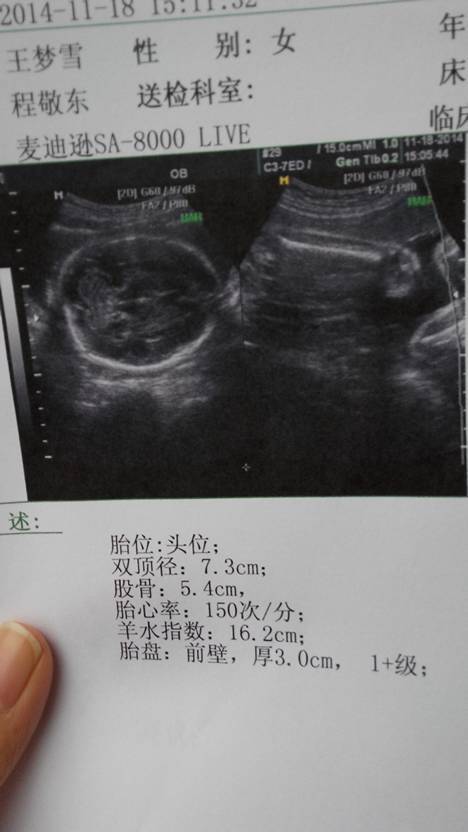

产科通用的公式:胎儿体重(千克)=双顶径(厘米)*0.9-5.2,你的宝宝双顶径7.3cm,所以体重应该是1.37kg左右了。 以上胎儿体重计算公式仅为胎儿体重估测 ,并不代表婴儿出生的实际体重。预测胎儿体重的目的在于要及早发现胎儿发育上存在的问题。一般来说,出生时的实际体重与预测体重会有正负10-...15%的误差。比如,出生体重4000克,其误差范围会为400克。也就是说,宝宝体重越大,误差范围也就越大。

大概是2.74斤